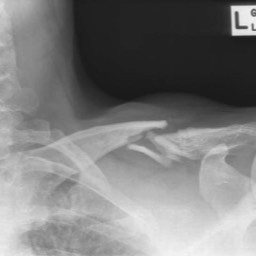

A 15 year old female fell from her pushbike causing a displaced left mid-shaft clavicular fracture. Seen 5 days later, plate & screws inserted 2 days later.

Image

DIsplaced fracture before surgery

DIsplaced fracture after surgery